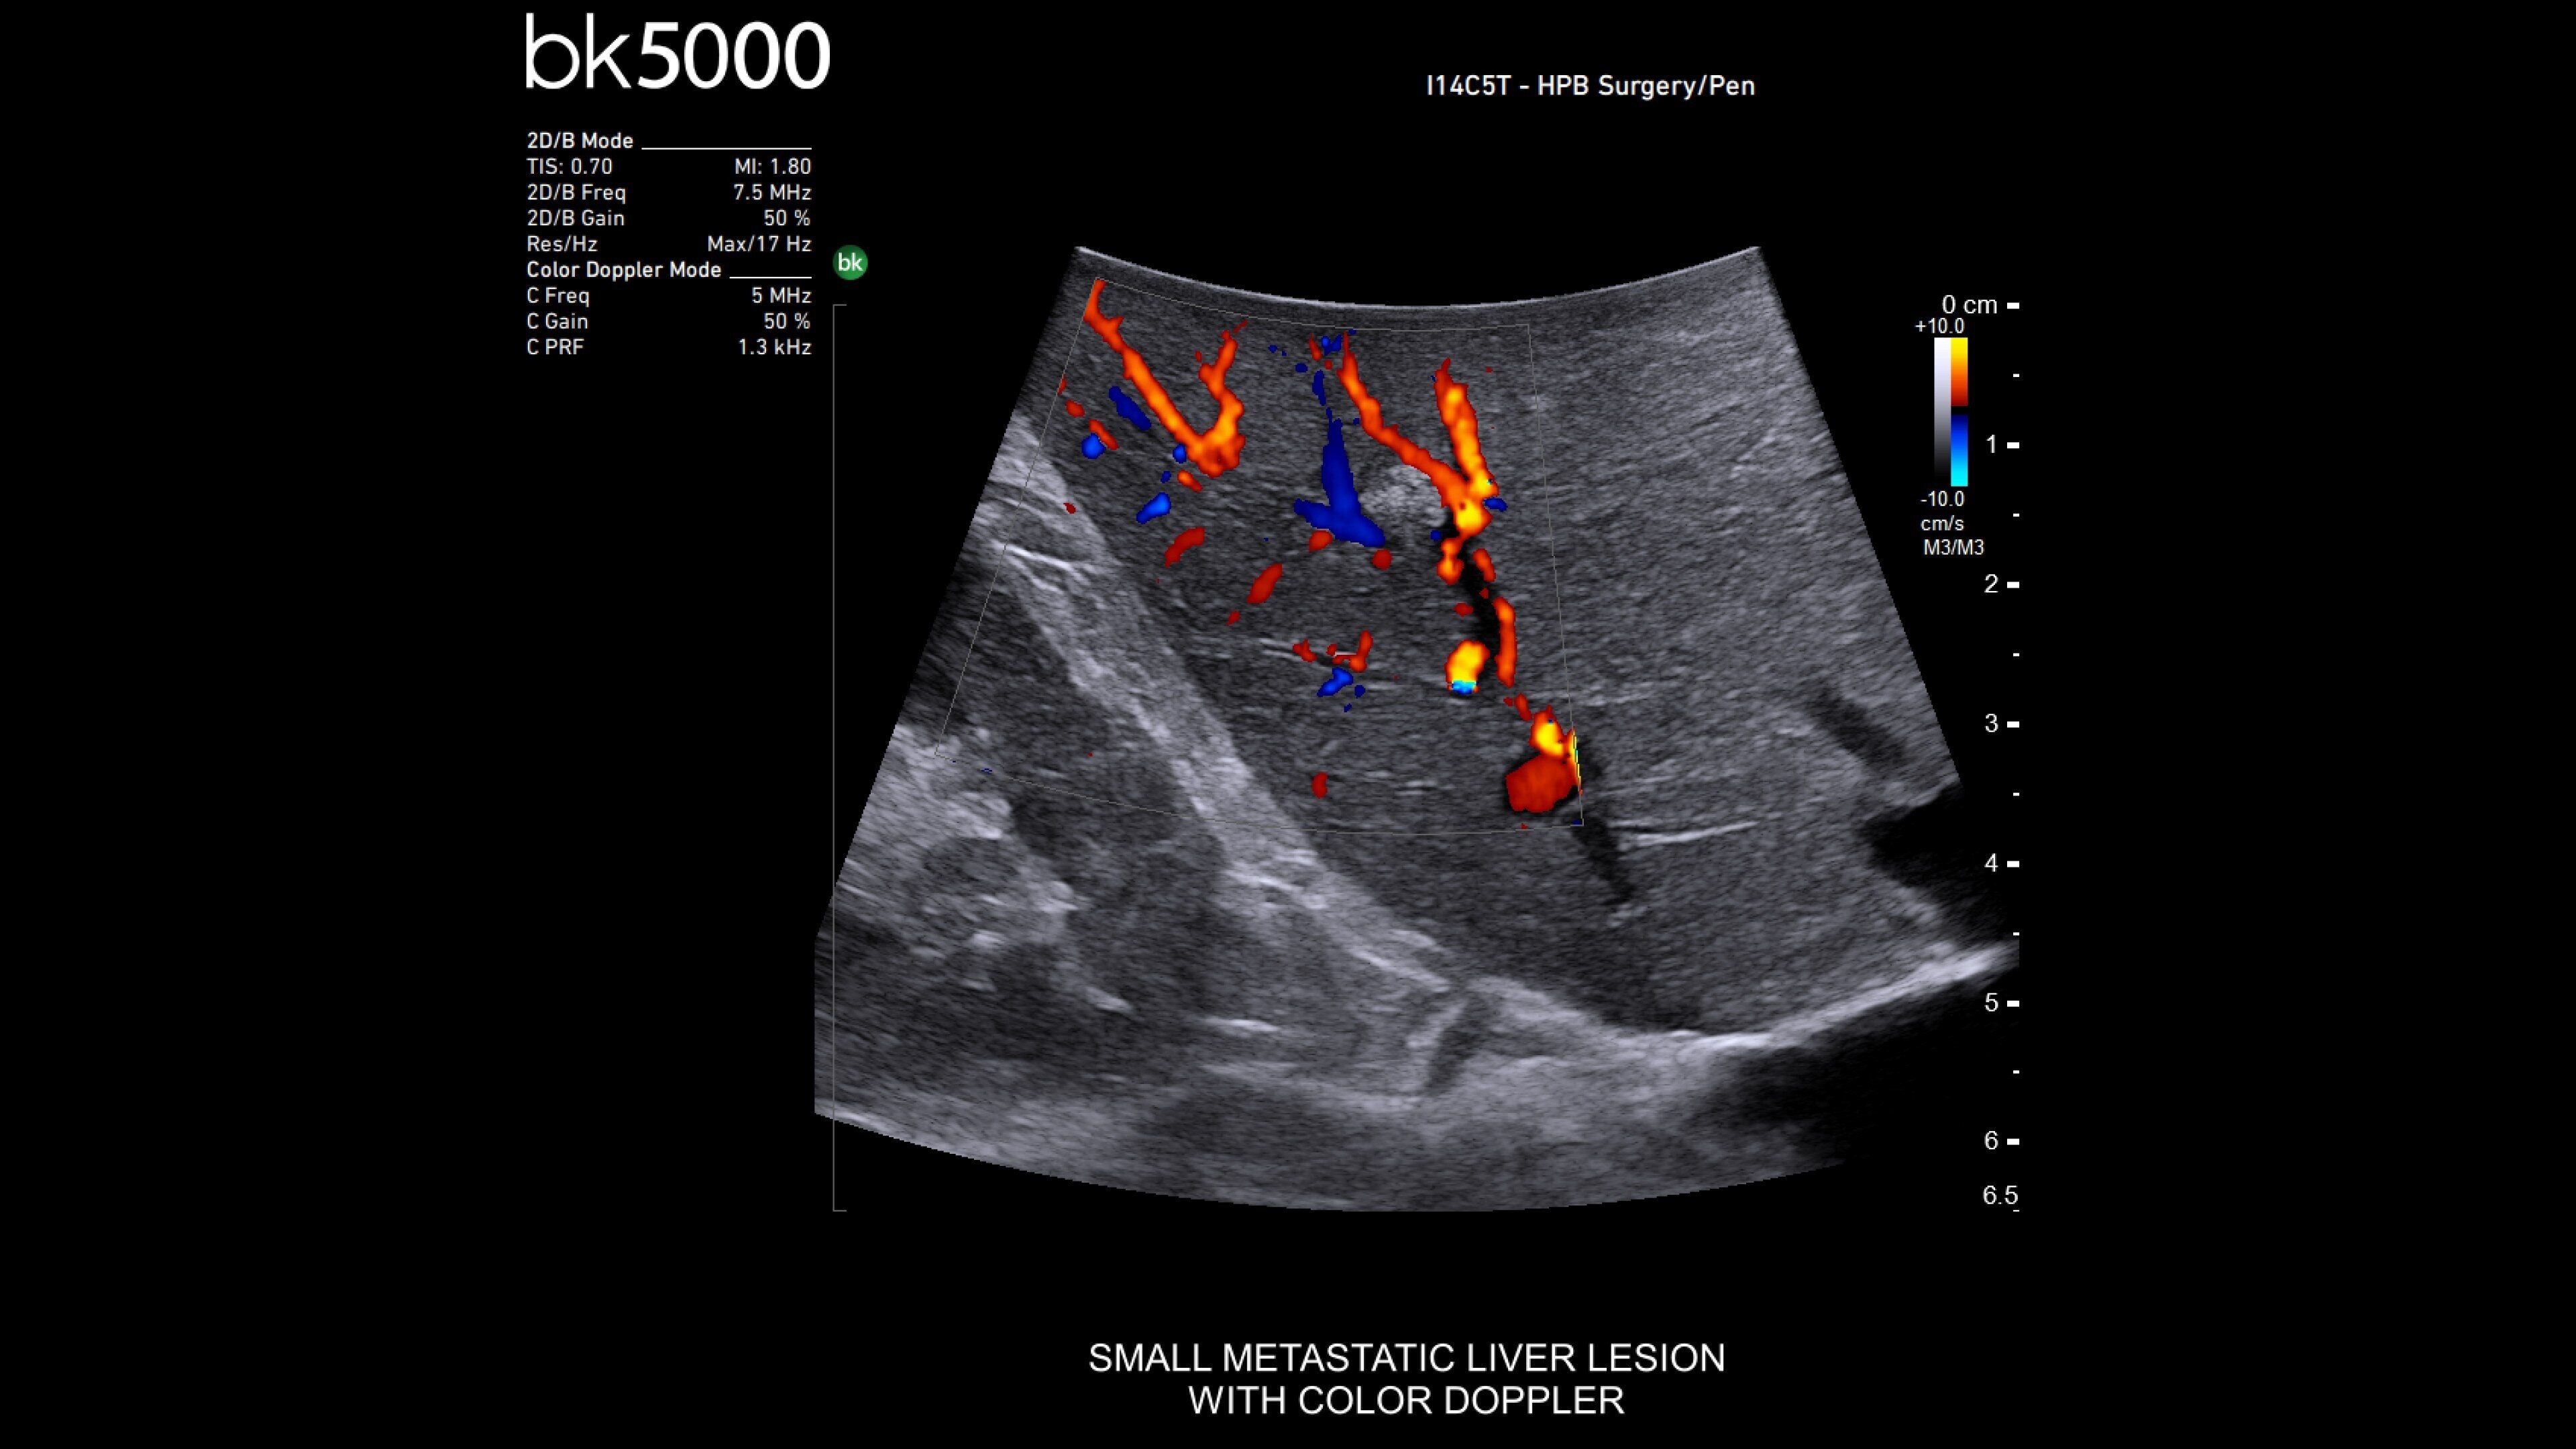

The bkActiv is a high-performance imaging system offering detailed, real-time surgical visualization. Refined through extensive research and user feedback, it supports remarkable imaging of areas of interest–neurosurgical (neuro-oncology, spine, neurovascular), urology (prostate, kidney, and bladder), hepatobiliary, colorectal, and pelvic floor.

It features technology such as Dual Live Compare for live image comparion, stored image compare, mirror image to see a live iUS image on the touch screen and sensitive color Doppler visualizes blood flow during complex surgeries.

Enhanced visualization for general surgery

The bkActiv ultrasound system delivers remarkable imaging for general surgery, including anorectal, robotics-assisted, and pelvic floor surgeries. Its advanced algorithms provide uniform image resolution and greater detail, while the remote control allows surgeons to adjust images within the sterile field. For anorectal surgeries, bkActiv offers high-definition imaging to visualize normal and abnormal anatomy, including anal sphincter injuries and rectal cancer. In robotics-assisted surgeries, the system's robotic transducers provide real-time, high-resolution imaging to locate and assess lesions and critical structures. For pelvic floor surgeries, bkActiv's advanced 3D architecture supports dynamic, real-time examination during procedures.